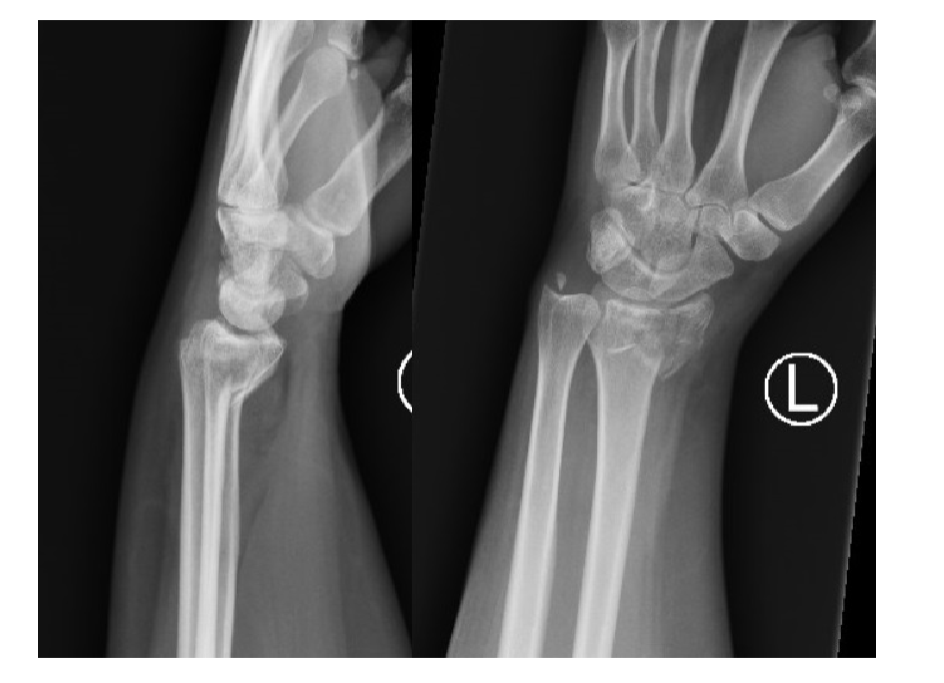

What is this?

Normal

Colles fracture

What kind of fracture would this lead to?

Smith fracture